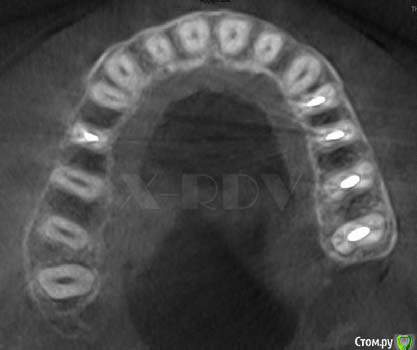

Гарриевич Опубликовано 9 марта, 2015 Поделиться Опубликовано 9 марта, 2015 Протейперы только появились ч клинике, буду пробовать по возможности одним штифтом. Есть какието нюанси?Дело в том, что этот метод обтурации к/к не дает герметизма, так как в большинстве случаем каналы корня у нас не круглые в сечении, а овальные. Вот хорошая картинка по этому поводуОМ - обтурационный материал, все что правее дебрис и пустотаhttp://s59.radikal.ru/i163/1503/1c/e666aef7fef9.jpg 3 Ссылка на комментарий

Паращук Роман Опубликовано 9 марта, 2015 Поделиться Опубликовано 9 марта, 2015 Дело в том, что этот метод обтурации к/к не дает герметизма, так как в большинстве случаем каналы корня у нас не круглые в сечении, а овальные. Вот хорошая картинка по этому поводуОМ - обтурационный материал, все что правее дебрис и пустота Самое интересное что и латералка и даунпак у некоторых будет выглядеть так же.)) Ссылка на комментарий